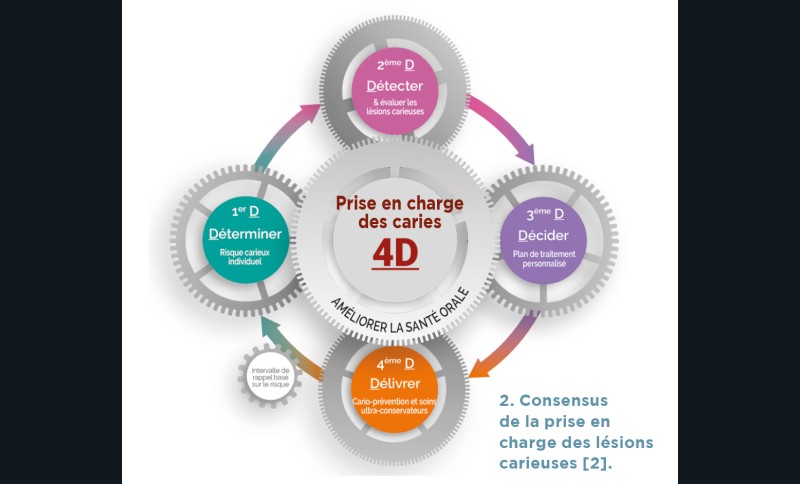

VRAI. Après le diagnostic des lésions carieuses, il faut évaluer le risque carieux individuel (RCI) du patient. A l’aide du CAMBRA ou de l’application Mi Dentistry, accessible gratuitement à tous depuis un smartphone (Android : https://play.google.com/store/apps/details?id=com.benoitballester.gc.miapp.alpha, iOS:https://apps.apple.com/fr/app/mi-dentistry-cra/id1454421681), le praticien peut aisément déterminer le RCI. Il s’agit de déterminer si le patient est à faible risque carieux ou à haut risque carieux. Ainsi, la prise en charge sera personnalisée et mieux adaptée (fig. 2).

Le choix de la prise en charge de la lésion carieuse dépend de trois critères fondamentaux : l’activité de la lésion carieuse (active ou arrêtée), la présence ou non de cavitation et l’accessibilité (site proximal difficile d’accès) (fig. 3).

La prise en charge de la lésion carieuse se fait :

- soit de façon non invasive : motivation du patient à l’hygiène interdentaire et utilisation de techniques non invasives de reminéralisation ;

- soit de façon micro invasive en utilisant les techniques d’érosion/infiltration ;

- soit de façon invasive a minima. Cette économie tissulaire peut se faire notamment avec l’utilisation de fraises adaptées et minimalement invasives (fig. 4).

Dans tous les cas, un monitoring doit être mis en place.